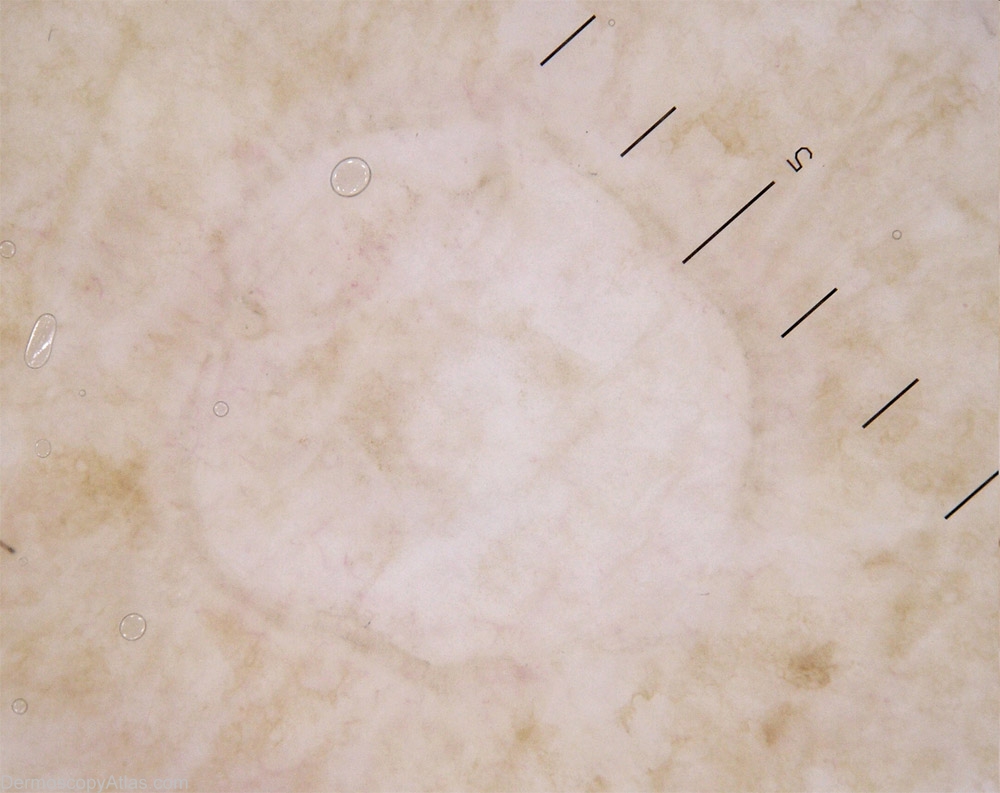

Image Number #2428 (Porokeratoses)

Site: Limbs

Diagnosis: Porokeratoses

Description: Numerous macules of different size. They are delimitated by a delicate border; some are erythematous.

History: This 57 years old lady complains of leg and arm lesions: they appear each summer when she spends much time outside bicycling. They are red and a bit itchy, and their number increases each year. They don't disappear completely during the winter. The exam reveals numerous small and well delimitated lesions small to middle size macules. Some of them seem irritated. It's a typical history and aspect of a Disseminated Superficial Actinic Porokeratoses.